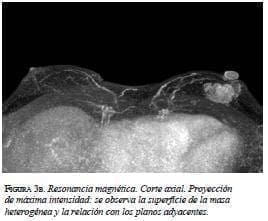

En la mamografía (figura 1a y 1b) se demostró una masa densa, irregular, de 3 x 2 cm en la región subareolar izquierda. Por ultrasonido (figura 2) se confirmó la pre-sencia de una masa sólida, hipoecoica e irregular. En la resonancia magnética (figura 3 a, b y c) se observó una masa hipercaptante, heterogénea, irregular, subareolar izquierda, de 3,5 x 2,5 cm, con curva de realce sospe-chosa tipo III. En todas las modalidades diagnósticas la lesión se clasificó según el sistema de datos y registro de imagen de mama (BI-RADS), como una lesión categoría V: altamente sospechosa de malignidad.